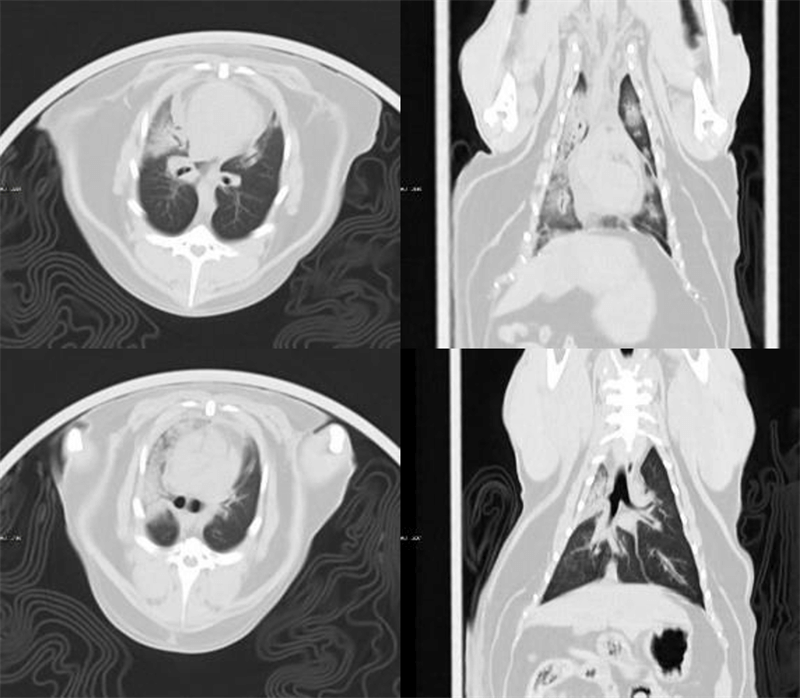

Clinical Gallery